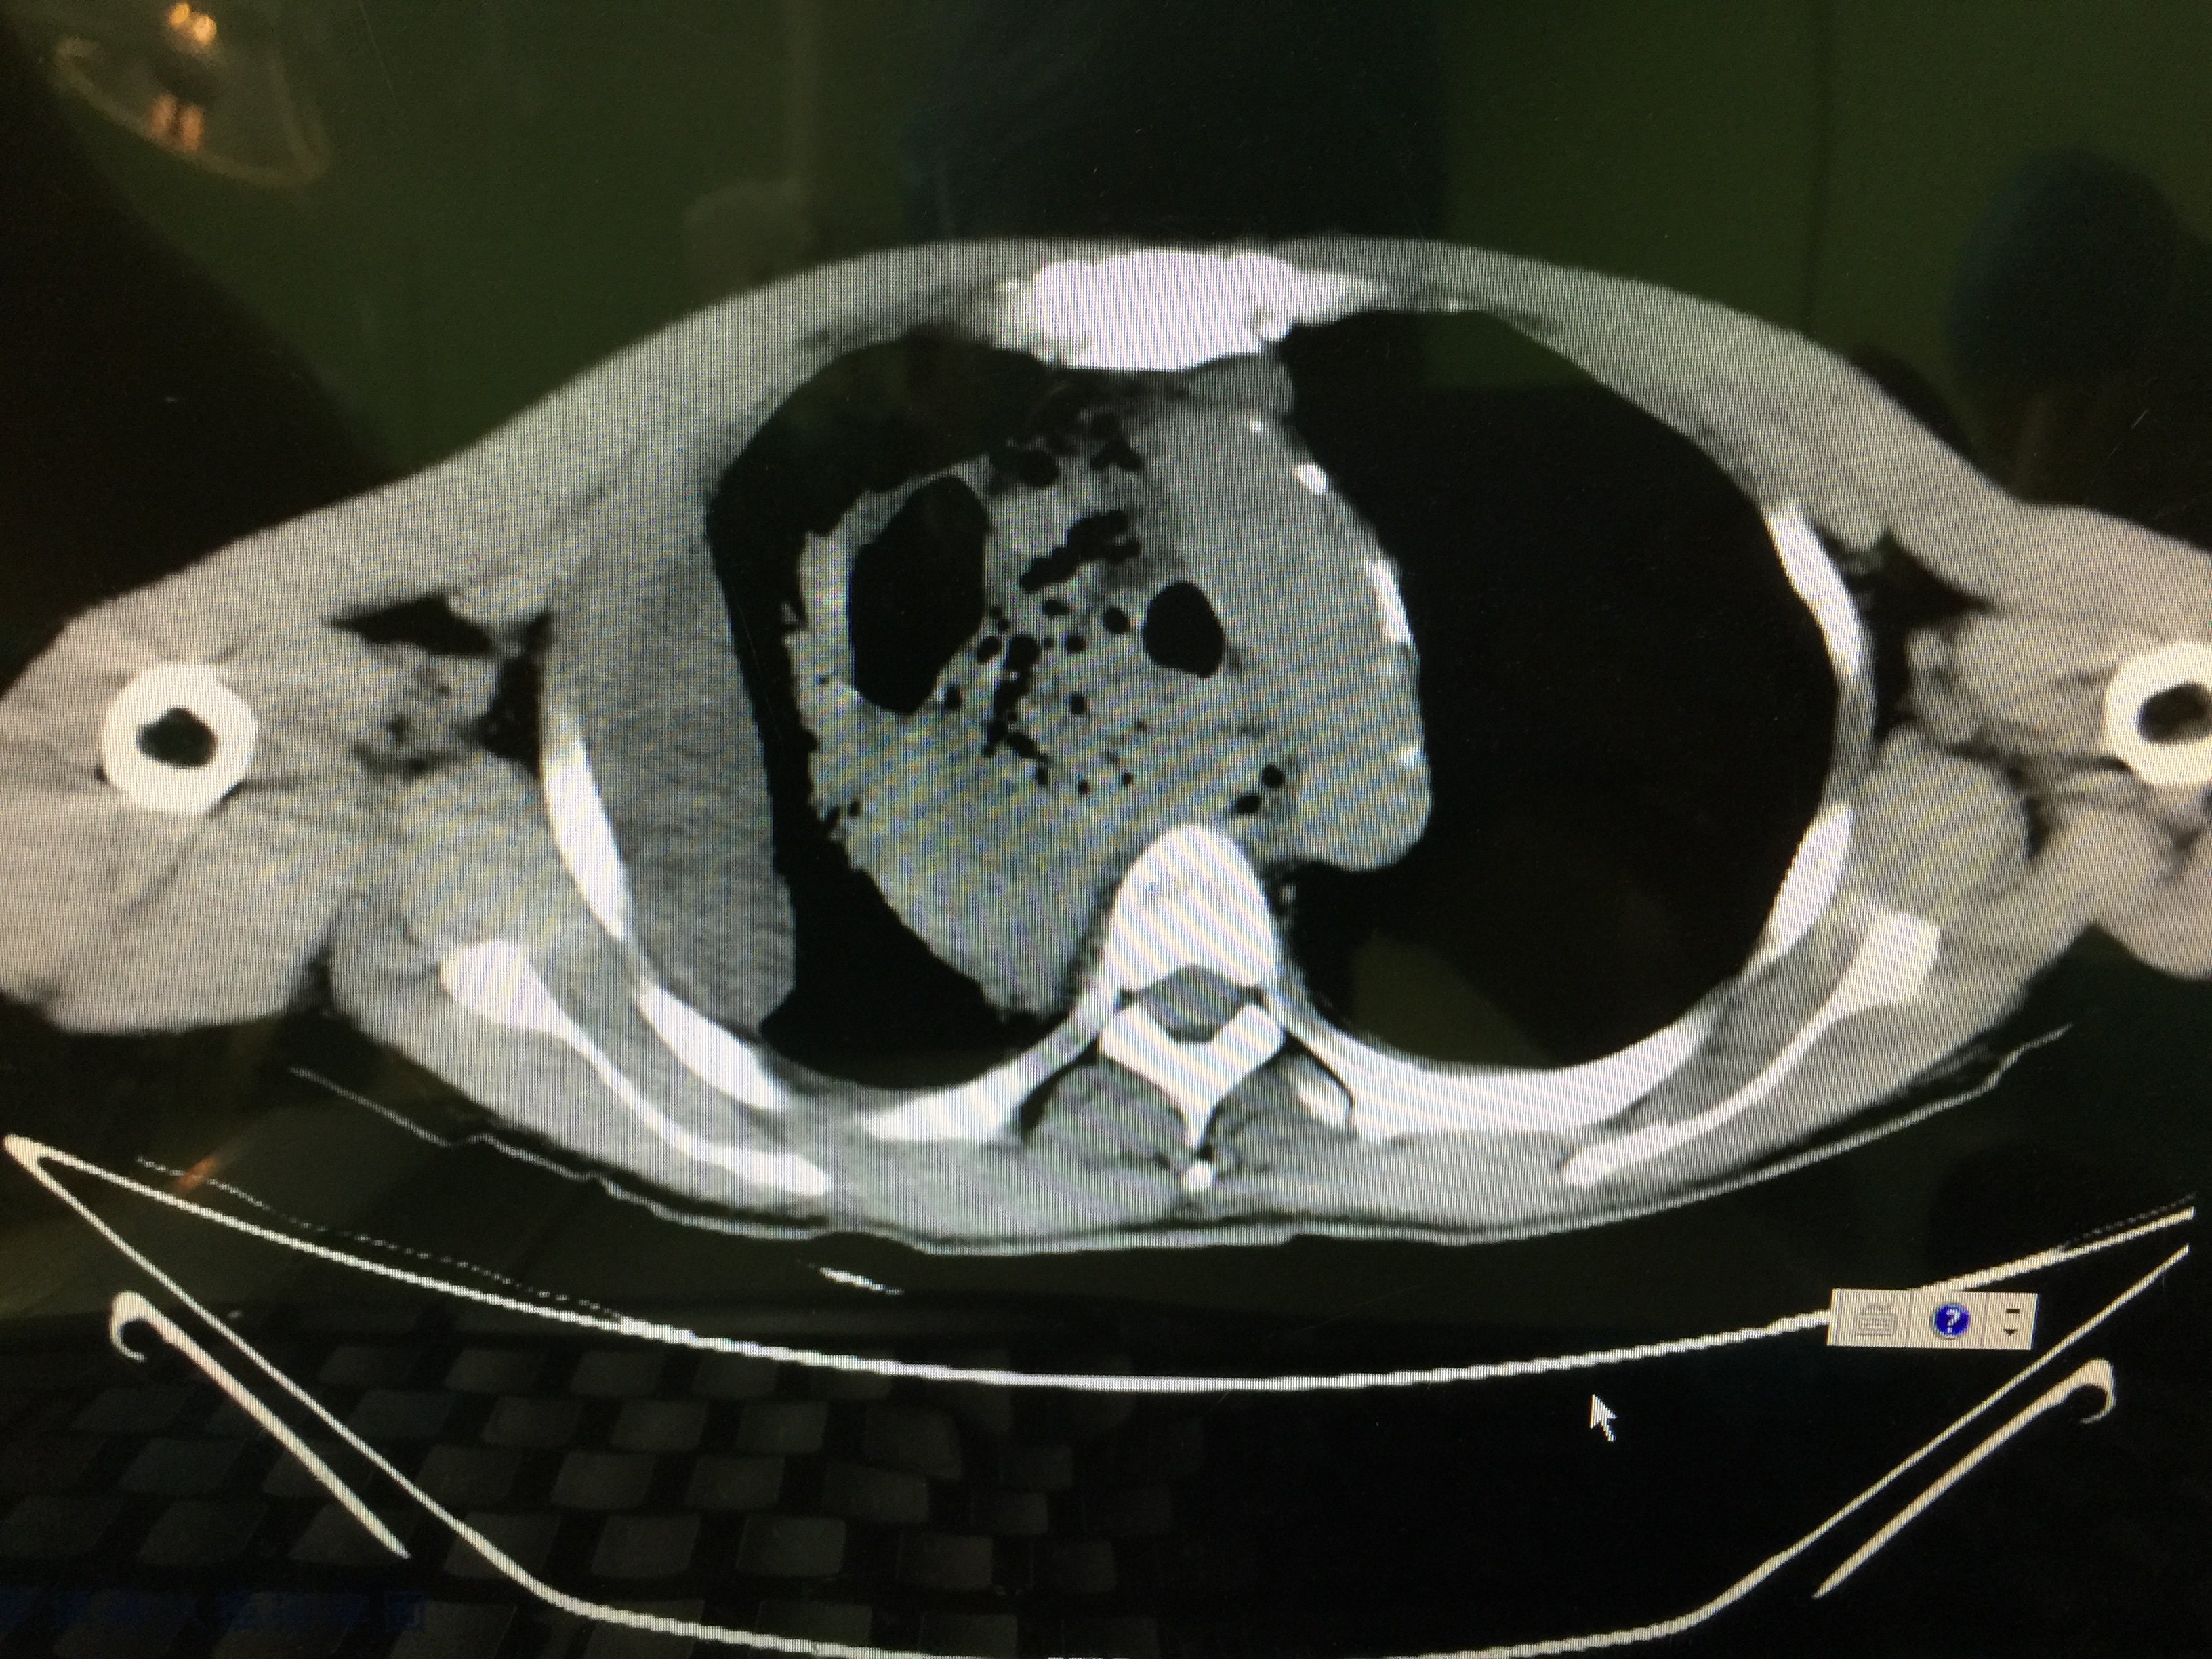

后在郑州某医院进行ct检查,结果提示:右上纵隔恶性占位,上腔静脉受侵